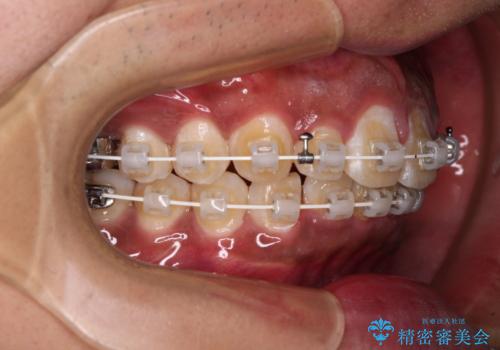

抜歯は行わず、補助装置を用いて上顎歯列全体を後方移動させ、ワイヤー装置にて奥歯の咬み合わせを改善していくこととしました。

正面や横から見た印象が同じで用であっても、奥歯の咬み合わせが理想的であるかどうかによって、治療の難易度は大きく異なります。

こちらの方も難易度のやや高い状態で、2年以上の期間が予想されましたが、想定通りの2年強で治療を終えることができました。